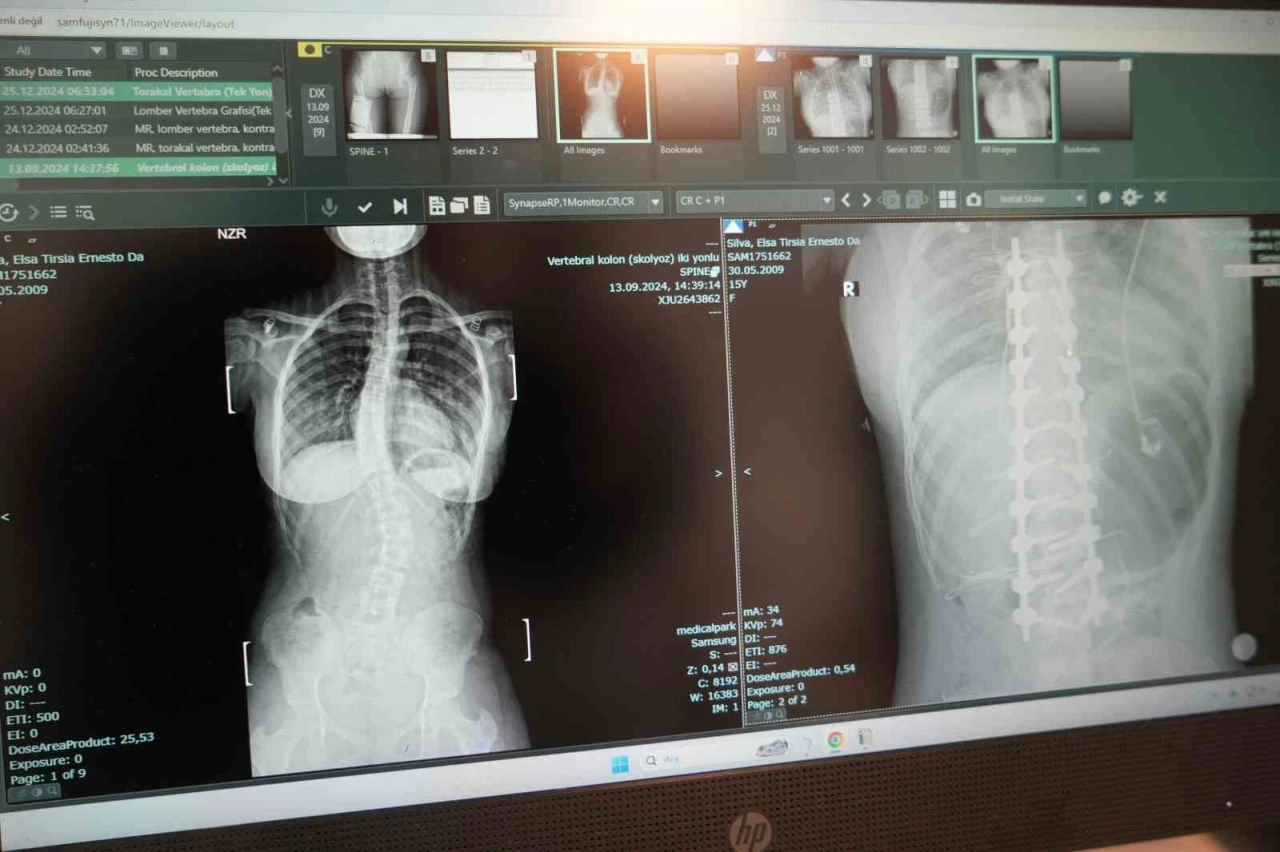

Soldaki öncesi sağdaki sonrası

Omurgasında 45 derece eğrilik bulunan skolyoz hastası 15 yaşındaki Elsa Silva, Angola’dan Samsun’a gelerek burada yapılan ameliyatla şifa buldu.

Hastanın ameliyatını gerçekleştiren Ortopedi ve Travmatoloji Uzm. Prof. Dr. Turgut Nedim Karaismailoğlu, "Hastamızda skolyoz mevcuttu. 2 ay önce bize geldi. Angola’da yaşıyorlar. Geldiğinde 45 derece bel eğriliği mevcuttu. Yaşı 15’ti ve bu yaşta ameliyat olması gerekiyordu. Hasta, ameliyattan sonra ikinci gün ayağa kaldırıldı. Üçüncü günde taburcu edildi. 15. günde dikişleri alındı. Bu ameliyatlar ağır ve dikkat isteyen ameliyatlardır. Bu konuda Türkiye’de son dönemde çalışan uzman sayısı arttı. Samsun’da bu imkan olduğu için çevre ülkelerden gelen hasta sayısında artış mevcut. Biz de onlara elimizden geldiğince cevap vermeye çalışıyoruz" dedi.